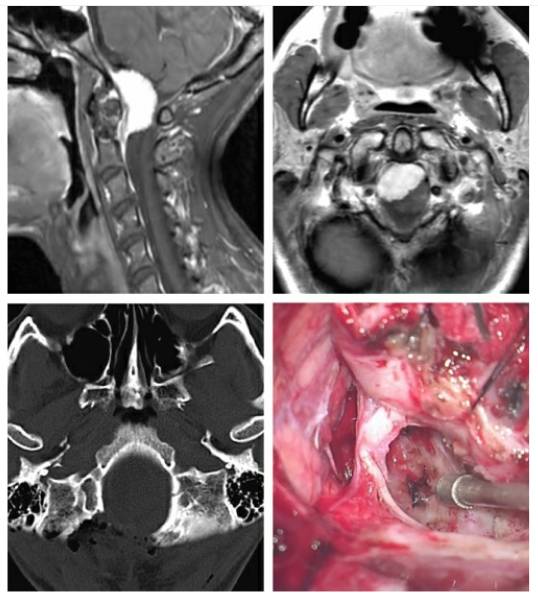

术前评估

MRI可显示肿瘤的头尾侧范围并指导枕下开颅的大小。另外,病变的腹外侧定位决定枕髁切除的必要程度。脑干及脊髓的水肿、肿瘤的钙化提示软膜侵犯;因为移除肿瘤对软膜无可避免有所骚扰,脑干、脊髓的水肿及肿瘤钙化也和术后神经功能下降的进展相关。对于这样的病例,笔者推荐进行次全切除——在软膜和血管周围留下一薄片肿瘤来保护软膜及穿支血管。包裹血管和肿瘤侵犯进入颈静脉孔(包绕颅神经)也是次全切除的指证之一。

图像评估还应包括CT或常规血管造影来判断肿瘤与毗邻血管(椎动脉,PICA的硬膜外或硬膜下起点)的关系以及椎动脉优势侧。这一信息用于判断同侧椎动脉在PICA起点以近阻断的安全性。切除高度钙化的肿瘤也是令人生畏的挑战,因其包裹神经血管结构而仅要求行姑息性减压手术。

图2. 一个脑膜瘤钙化的年轻患者,观察数年直到症状严重影响其日常生活(上图)。患者在外院首次尝试切除肿瘤以失败告终。来笔者院尝试再次手术。肿瘤高度钙化使减压十分棘手,最终采用磨钻磨除肿瘤核心部分。在从脑干表面移除肿瘤包膜时,笔者不小心损伤了被包裹的椎动脉。这一激进做法导致了术后脑干梗死,最终患者不幸死亡(下图)。这一病例告诫笔者枕骨大孔区高度钙化的肿瘤减压比积极切除更重要。